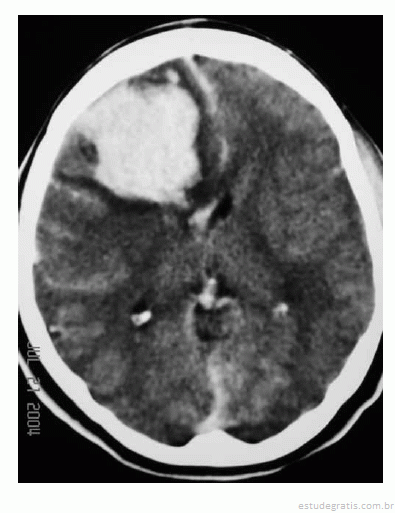

Uma mulher de 29 anos de idade teve sua gestação interrompida com 35 semanas, mediante parto cesariano, por ter apresentado quadro compatível com a doença hipertensiva específica da gravidez. No quinto dia de pós-operatório, apresentou importante dor de cabeça seguida de crises convulsivas; na avaliação laboratorial, foram atestadas plaquetopenia e alteração da função hepática. Ela foi levada à unidade de terapia intensiva, onde o plantonista observou hemiparesia esquerda e solicitou uma tomografia de crânio sem contraste, que é reproduzida abaixo.

Com base nessas informações, julgue os itens que se seguem.

O exame de neuroimagem evidencia volumoso abscesso cerebral.Comentários